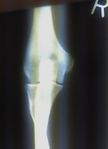

Close-up radiograph, right elbow-joint